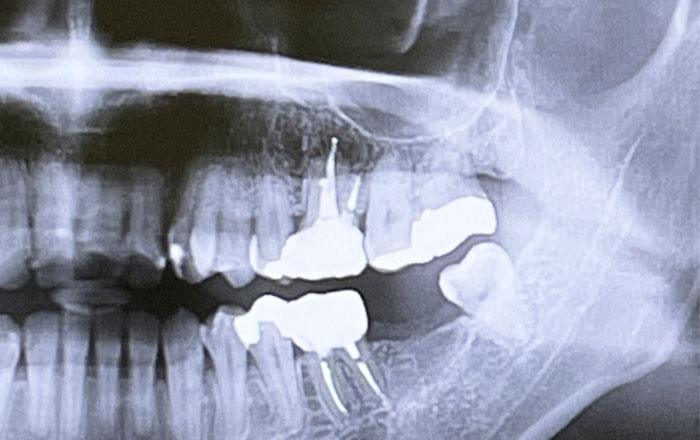

CT画像とお口の中の型(またはスキャンデータ)をもとに作製され、インプラントを入れるべき位置にあらかじめ小さな穴が開けられています。

インプラント治療で心配されるリスクの一つが、神経や血管の損傷(※)です。特に下顎には下歯槽神経(かしそうしんけい)という神経が通っており、これを傷つけると下唇や顎にしびれが残ってしまうことがあります。

また、上顎では上顎洞(じょうがくどう)という空洞に近いため、インプラントが突き抜けてしまうリスクも考慮しなければなりません。

まず、1.患者さんの希望や不安をヒアリングし、歯科用CTで顎の骨や神経、血管の位置、上顎洞との距離を撮影していきます。

続いて、2.コンピューター上で骨の厚みや神経との距離を確認しながら、安全で理想的なインプラントの埋入位置を決定します。この段階で、患者さんにもシミュレーション画像を見せながら説明を行う歯科医院も多いでしょう。

また、前述のとおり、下顎の奥歯付近は下歯槽神経に近く、上顎は上顎洞に近いため、これらの部位では特に用いられることが多いと言えるでしょう。